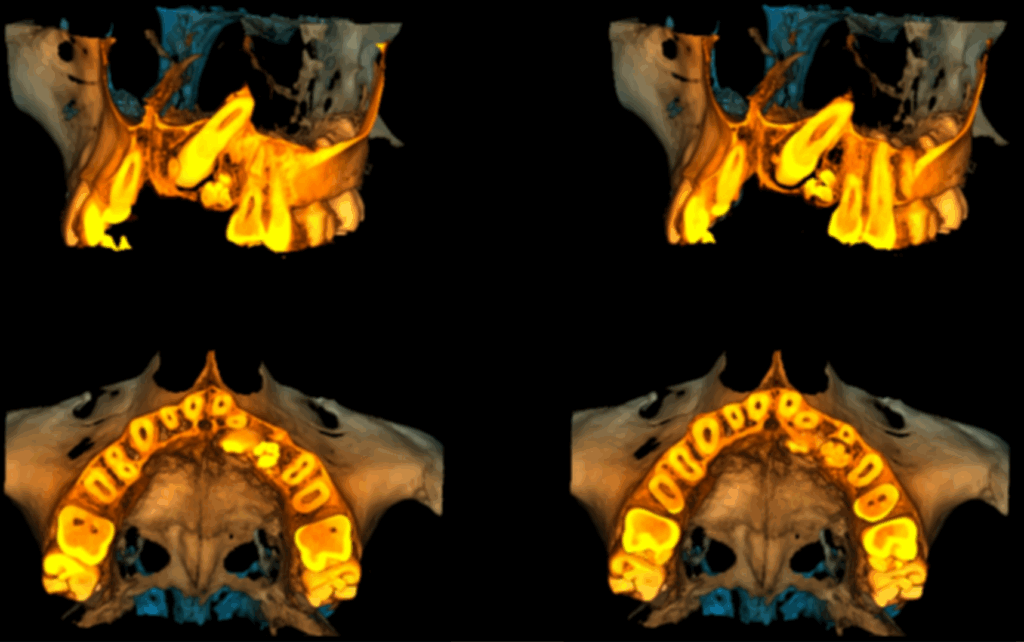

En la radiografía panorámica (Figura 1), se aprecia imagen radiopaca circunscrita con un halo radiolúcido, de limites definidos, proyectado en tercio medio y apical de pieza 53, observándose en el interior múltiples dentículos.

Radiografia Panorámica